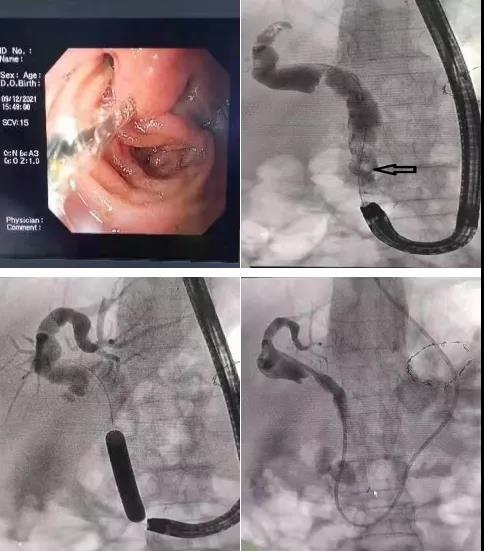

近日,消化內二科成功開展首例畢Ⅱ式胃大部切除術后復發難治性膽總管結石的ERCP取石手術。

患者81歲高齡女性,既往胃大部切除畢Ⅱ式吻合術后30余年,因發熱、腹痛入院,診斷為膽總管結石、急性梗阻性化膿性膽管炎?;颊叽嬖诟啐g、感染性休克等情況,病情復雜危重,蓋偉主任立即爭分奪秒組織科內專家仔細分析討論病情,決定首選ERCP取石術。

與家屬充分溝通后,蓋偉主任和田宗彪主治醫師開始內鏡下取石術,交替使用十二指腸鏡和胃鏡找到改道后的十二指腸乳頭,通過胃鏡完成插管、乳頭擴張成型、取石及鼻膽管置入,順利完成手術。術后,患者腹痛、發熱、黃疸等癥狀消失,三天后順利出院。